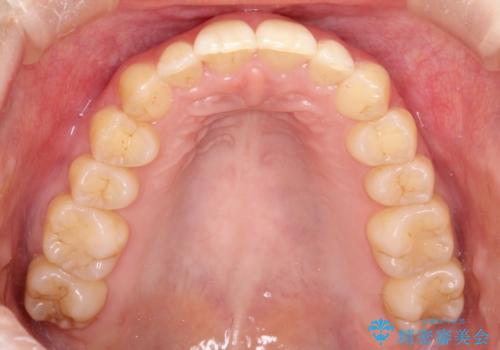

出ている前歯をインビザラインにて引っ込める

インビザラインにて上顎の歯を全体的に後方に移動させて前歯を引っ込める計画としました。

使用時間を守っていただけたので、比較的スムーズに矯正を終了することができました。